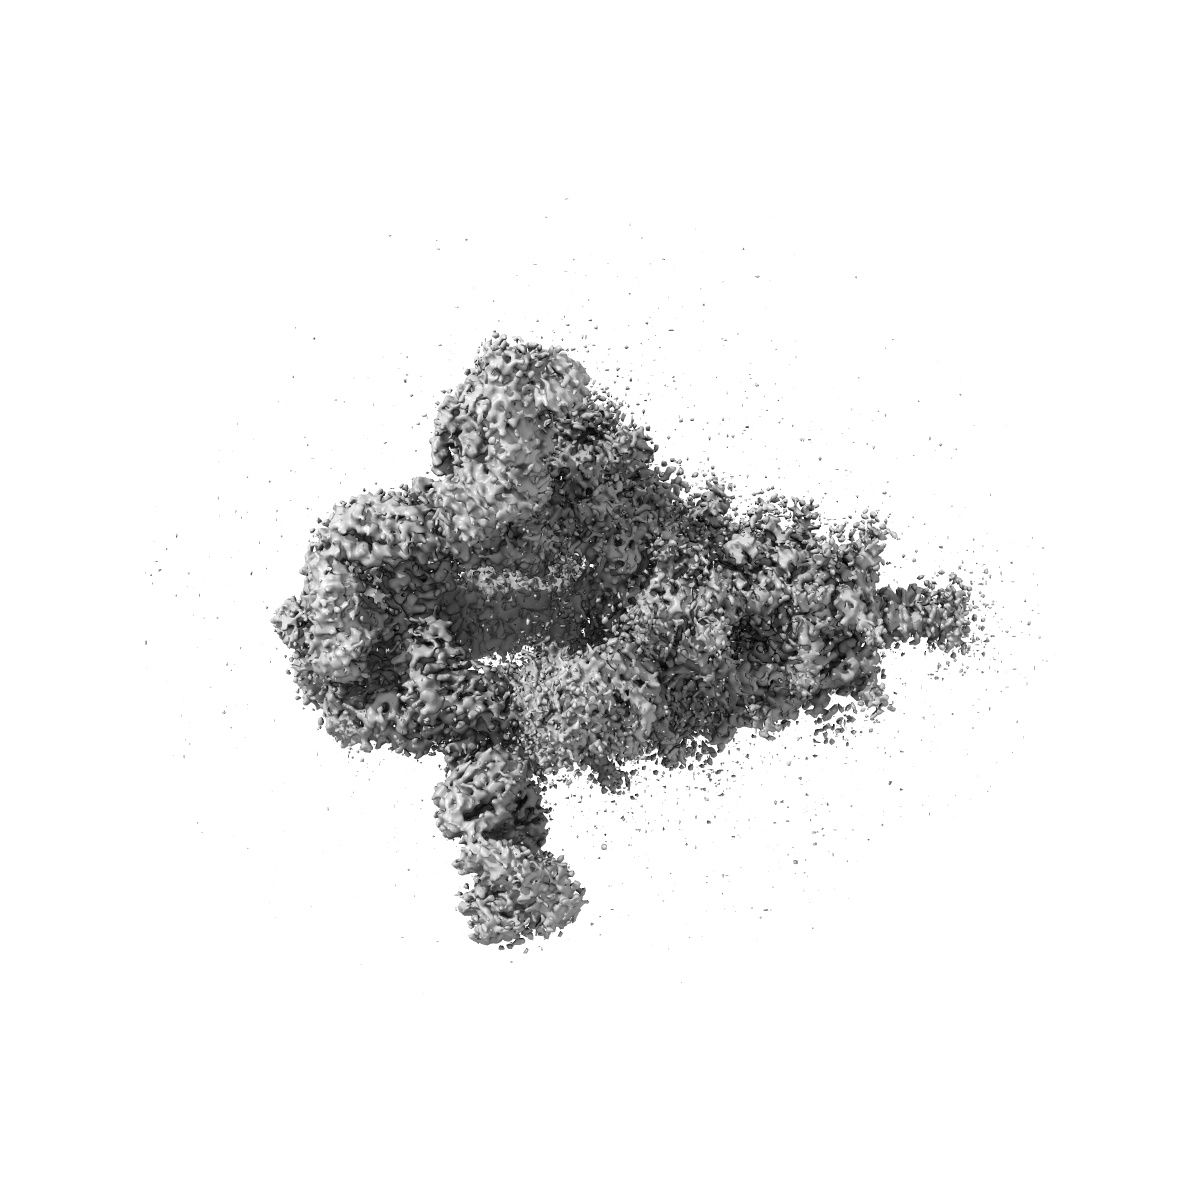

Cryo-EM structure of SARS-CoV-2 Delta Spike protein in complex with BA7054 and BA7125 fab

Single-particle3.2 Å

Sample: Cryo-EM structure of SARS-CoV-2 Delta Spike protein in complex with BA7054 and BA7125 fab